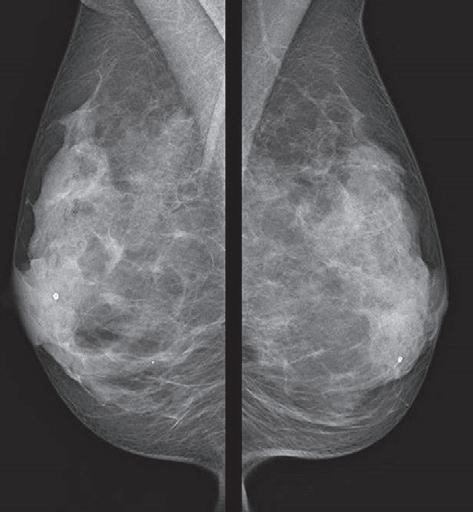

Übliche Mammographie: Patientin mit beidseitig sehr dichtem Drüsenkörper (helle Areale) und somit deutlich erschwerter Beurteilbarkeit in der normalen Mammographie. lage auf einer MRT-Liege, in die Vertiefungen für beide Brüste eingelassen sind. Um Veränderungen im Brustgewebe sicher beurteilen zu können, wird ein sehr gut verträgliches Kontrastmittel in die Armvene gespritzt. Die Untersuchung dauert etwa zwanzig Minuten.

Selbe Patientin im Mamma-MRT: Der dichte Drüsenkörper ist in der morphologischen T2-Sequenz des MRTs (links) gut zu sehen. In der für die Tumorsuche entscheidenden dynamischen MRT-Sequenz nach Kontrastmittelgabe (rechts) sieht man keinerlei Anreicherung des Drüsenkörpers, was in diesem Fall glücklicherweise einen bösartigen Tumor sicher ausschließt. Bösartige Tumore präsentieren sich im Mamma-MRT typischerweise mit einer oftmals irregulären oder ringförmigen Kontrastmittelaufnahme innerhalb des Gewebes und können dann sehr gut auch im dichten Drüsenkörper erkannt werden.